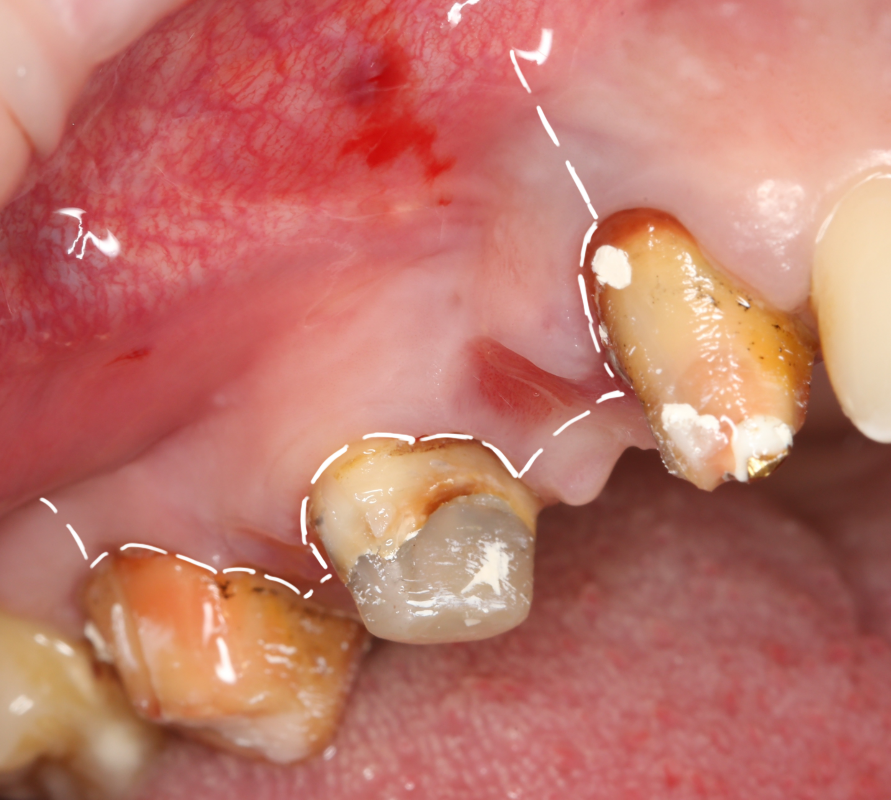

Синуслифтинг и удаление зуба

В некоторых случаях мы можем сочетать операцию синуслифтинга с удалением зуба. Это значительно сокращает сроки имплантологического лечения. Данная методика применяется при невозможности проведения немедленной имплантации одновременно с синуслифтингом.

Необходимым условием для проведения этого вмешательства является стадия ремиссии воспалительного процесса в области удаляемого зуба, отсутствие или небольшие размеры очагов хронического воспаления в прикорневой зоне (рис 49, 50, 51):

Рисунок 49, 50, 51. Проведение операции синуслифтинга одномоментно с удалением зуба: слева – скелетирование стенки верхней челюсти, подготовка к удалению зуба, в центре – лунка удаленного зуба (виден небольшой очаг деструкции костной ткани вследствие хронического периодонтита), справа – заполнение субантральной полости спейсером.